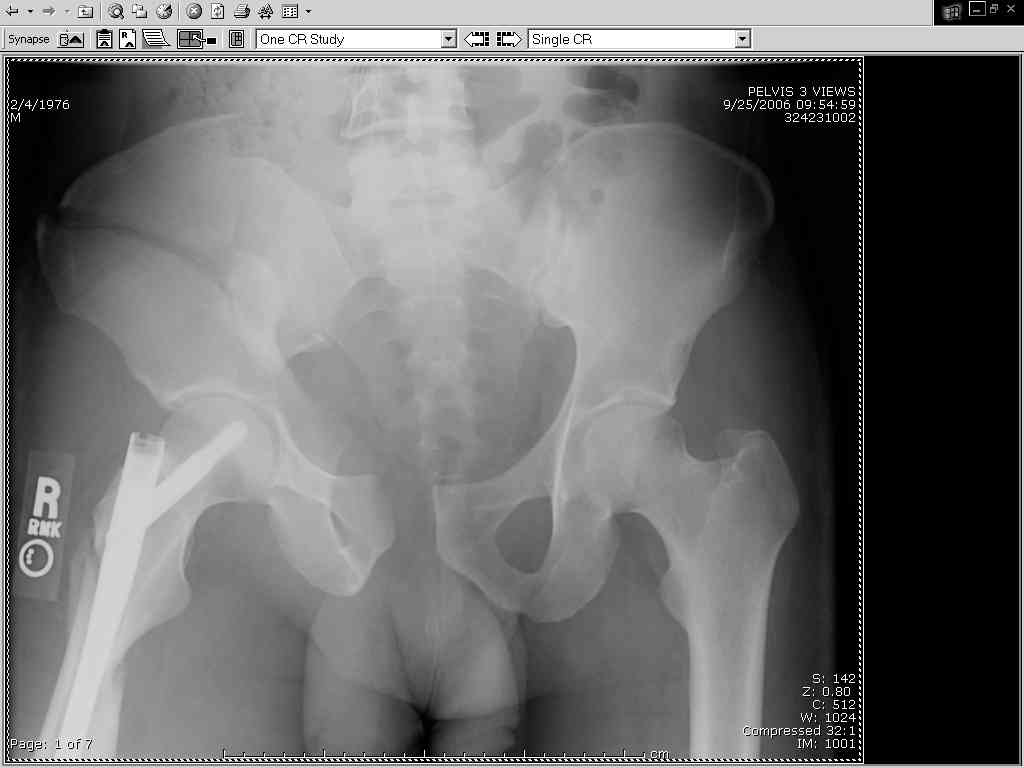

Thanks Adam - I agree it's not a pure APC (is there really such thing as a pure force vector strictly in the x,y or z plane?). I stand corrected. Maybe a hybrid APC (ext rot of L hemipelvis, symphysis disruption, ext rot of R anterior innominate) plus vertical shear as well with 3 or-so cm of cephalad migration of the R ilium. Maybe just "C-type".....

It almost looks to me like an extra-articular both column fx, in addition to the pelvic component. It has the typical triangular fragment and the OO view has a hint of the spur. You may be able to get it all with plates. I would consider fixing the crest first, then a long plate for both symph and iliac portion. SI may close with reduction of symphisis. Looks like the inferior portions are intact. I like your plan as well. You will probably solicit lots of opinion. Good luck. Look forward to post op view.

My current plan is supine, ORIF symphysis with as close to AFT reduction as possible, then fix the R ilium via lat window Ilioing.

approach with lags in the solid crest bone, 2 plates (one along pelvic brim and one up on the inside of the crest), then, if I have good posterior reduction and can get a good view of the ICD on my lat sacral view with image, L side perc SI screw, if not then anterior L SI approach and 2 anterior plates.